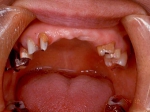

片側2歯欠損 主訴-入れ歯を使ってみたが違和感強くてダメ。固定のものにしたい。術前下顎口腔内(鏡像)